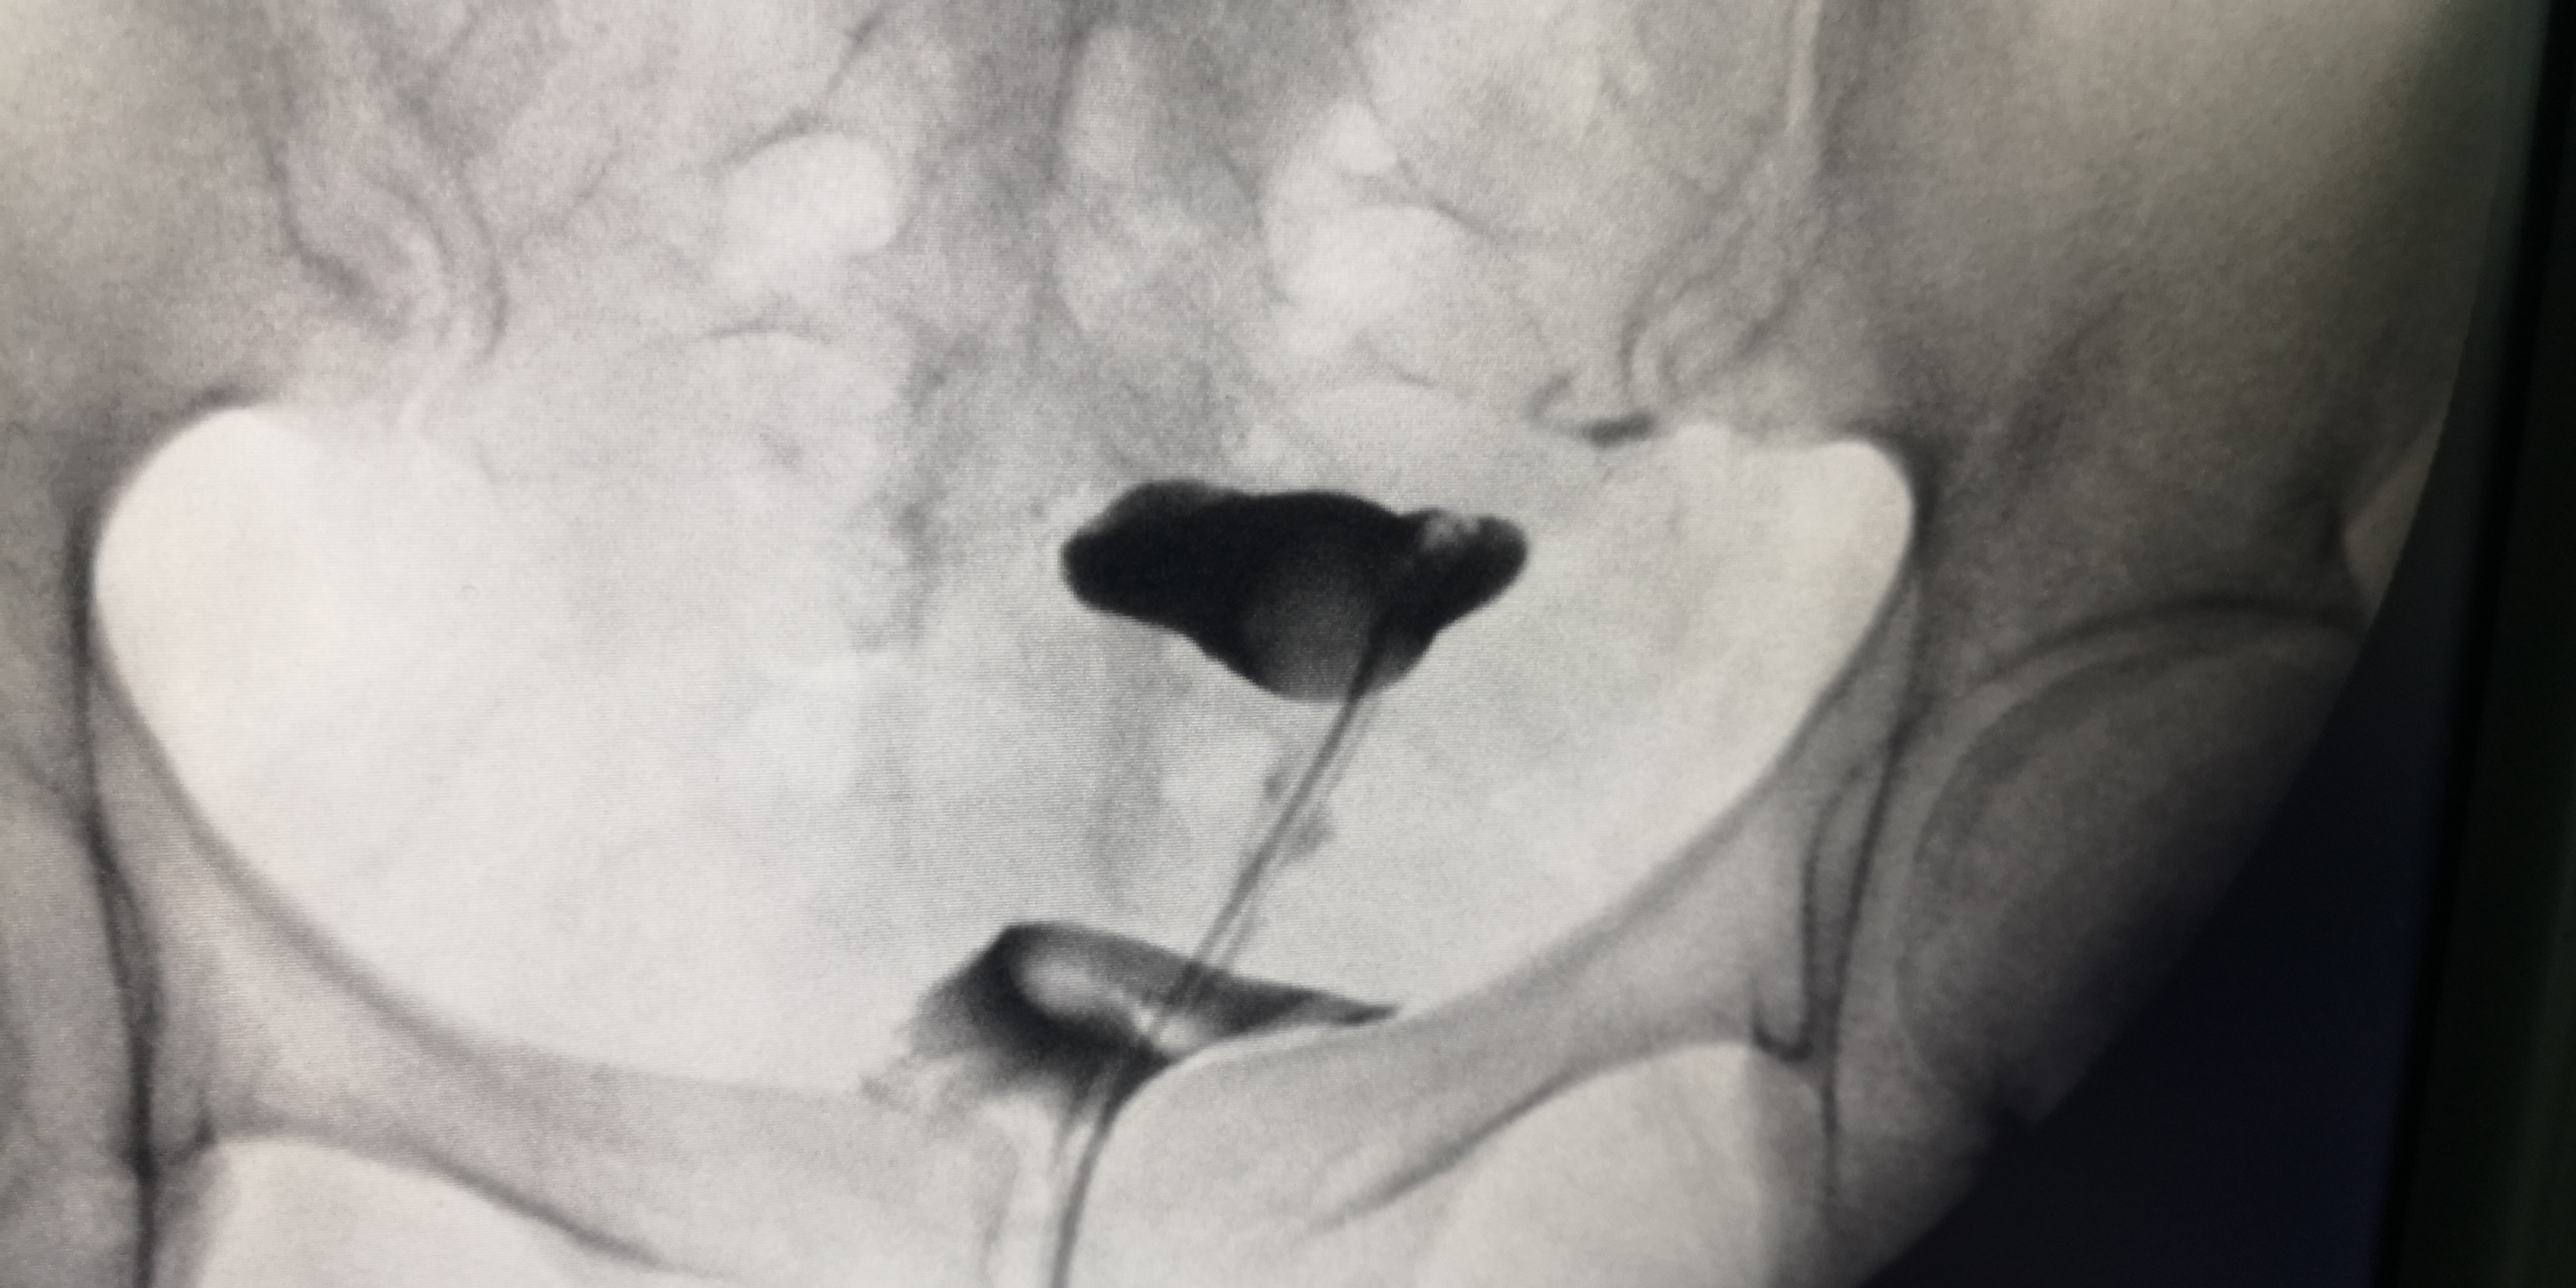

3月30日,我院妇产科成功开展了第一例子宫输卵管造影术。该手术由弋矶山医院生殖中心胡卫华主任专家团队的徐庆阳主任诊疗、余小英博士和我院妇产科医生共同完成。手术过程顺利,术中患者呼吸、心律平稳,无头晕胸闷、恶心呕吐等不适。术中清晰显示了患者子宫腔形态及输卵阻塞部位,从而明确了该不孕症患者的下一步治疗方向。

经X线的子宫输卵管造影术,是通过导管,向宫腔、及输卵管注入造影剂,利用X线诊断仪行X线透视及摄片,根据造影剂在子宫腔、输卵管、及盆腔内的显影情况,来了解输卵管是否通畅、阻塞部位及宫腔形态的一种检查方法。

子宫输卵管造影术损伤小,在有经验的医师操作下,并附以数字X光机的应用,能对输卵管堵塞作出正确诊断,准确率达80%,且具有一定的治疗作用。是用来了解输卵管是否通畅、通畅的程度及具体堵塞部位的最常用的检查方法。